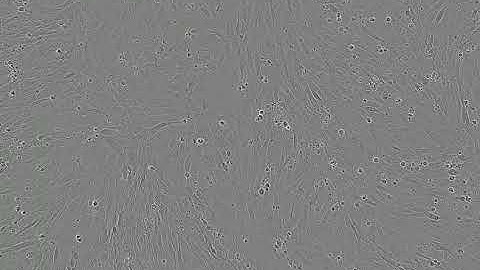

Cell Differentiation Part 2